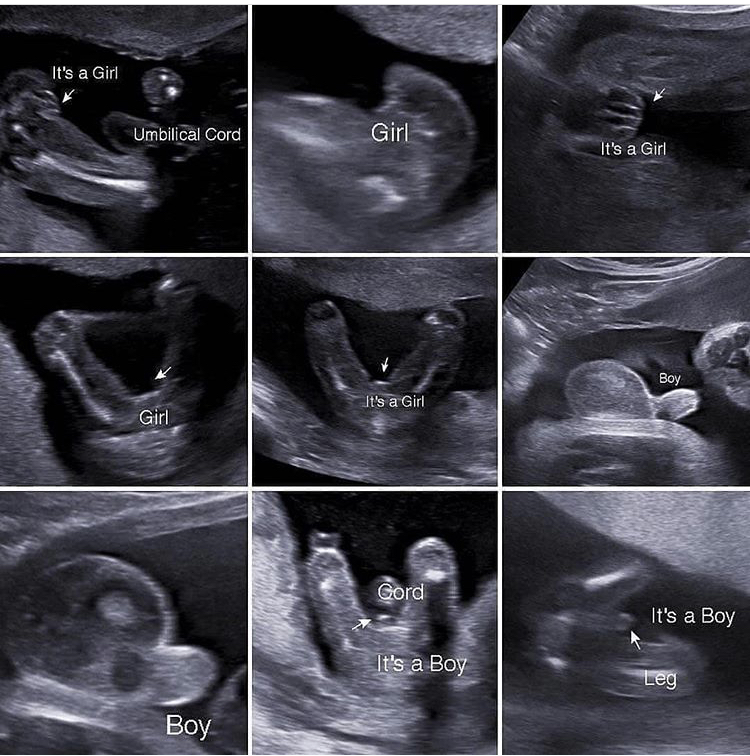

Tasha в Благополучная беременность 7 лет Пол ребёнка на узи Пол малыша Девочки, попалась такая картинка в интернете, многим будет интересно, наверное :) Посмотрите еще 20 записей на эту тему Отменить Ответить Sunny Bunny мой вообще не похож ни на кого)))) 05.06.2019 Ответить Ну точно же мальчик, да?😅 Пол в 14 недель Чаты Беременных Выберите чат: Январята-2026 Февралята-2026 Мартята-2026 Апрелята-2026 Майчата-2026 Июнята-2026 Июлята-2026 Августята-2026